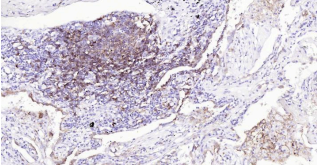

HLA-DR, like other MHC class II molecules, is a transmembrane glycoprotein composed of a 36 kDa alpha chain (DRA) and 27 kDa beta chain (DRB). The alpha chain gene contains 5 exons. Exon 1 encodes the leader peptide, exons 2 and 3 encode the two extracellular domains, and exon 4 encodes the transmembrane domain and the cytoplasmic tail. DRA does not have polymorphisms in the peptide binding part and acts as the sole alpha chain for DRB1, DRB3, DRB4 and DRB5. Within the DR molecule the beta chain contains all the polymorphisms specifying the peptide binding specificities. Hundreds of DRB1 alleles have been described and typing for these polymorphisms is routinely done for bone marrow and kidney transplantation. HLA-DR is expressed primarily on antigen presenting cells such as B lymphocytes, monocytes, macrophages, thymic epithelial cells and activated T lymphocytes. Three loci, DR, DQ and DP, encode the major expressed products of the human class II region. The human MHC class II molecules bind intracellularly processed peptides, present them to T-helper cells, and have a critical role in the initiation of the immune response.